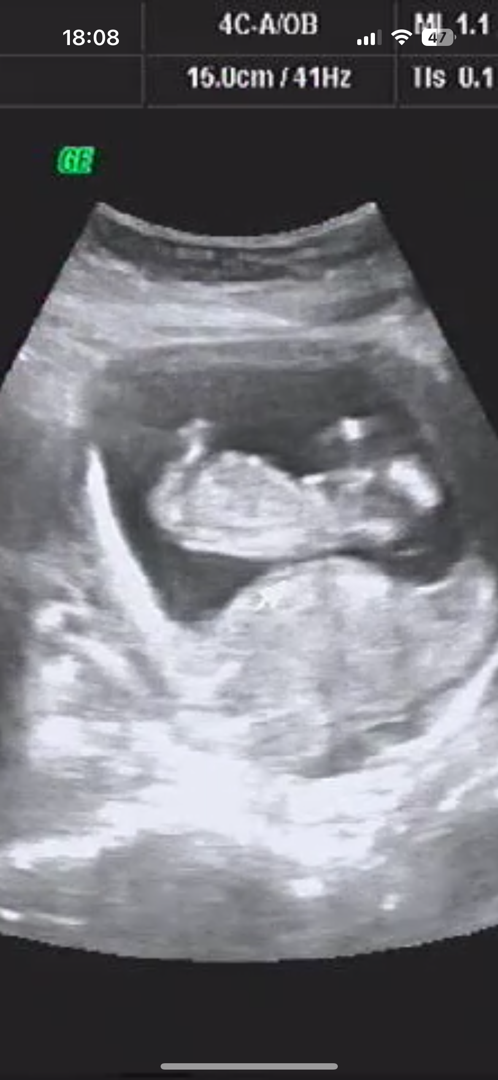

12주 3일 각도법 아들일까요 딸일까요 확인해주세용~~

생식기가 보이지 않는 초음파로는 각도법을 판단하기는 어렵습니다 아가가 숨기고 있네요 부끄러운지